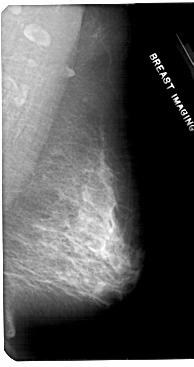

A_1804_1.LEFT_MLO

LEFT_MLO LINES 5311 PIXELS_PER_LINE 2971 BITS_PER_PIXEL 12 RESOLUTION 43.5 OVERLAY

FILE: A_1804_1.LEFT_MLO.OVERLAY

TOTAL_ABNORMALITIES 1

ABNORMALITY 1

LESION_TYPE MASS SHAPE ARCHITECTURAL_DISTORTION MARGINS SPICULATED

ASSESSMENT 4

SUBTLETY 1

PATHOLOGY MALIGNANT

TOTAL_OUTLINES 1

BOUNDARY